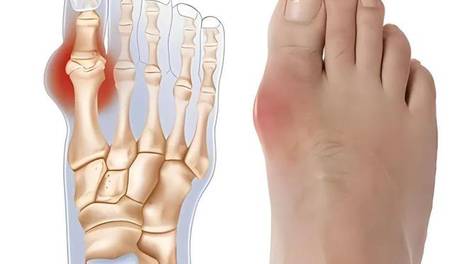

痛风引起慢性肾衰竭怎么办?

药物治疗:对于痛风引起的慢性肾衰竭,药物治疗是基础。手术治疗:在尿酸结石引起严重阻塞或其他需要手术干预的并发症时,手术治疗可能是必要的。定期检查:对于痛风患者,定期复查尿酸水平和肾功能,及时发现问题并进行治疗…